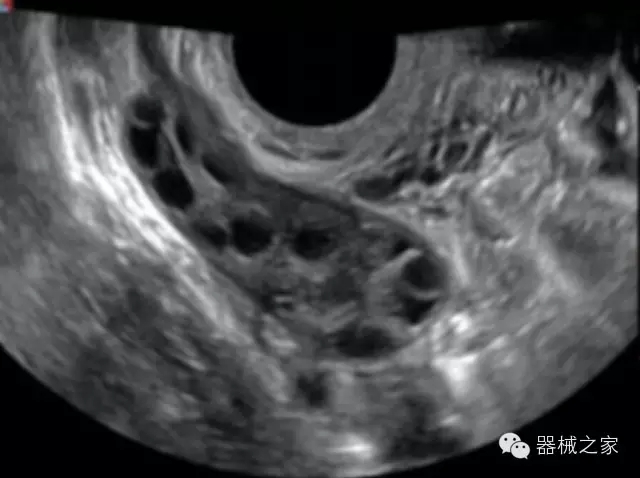

臨床圖片賞析

產(chǎn)品特點(diǎn)

·全球目前唯一一款配備主機(jī)雙探頭接口,整機(jī)重量(含電池)在5公斤以內(nèi)的便攜式彩超;

·獨(dú)有的HoloTM PW 實(shí)時(shí)3取樣門PW成像技術(shù),精確進(jìn)行血管診斷;